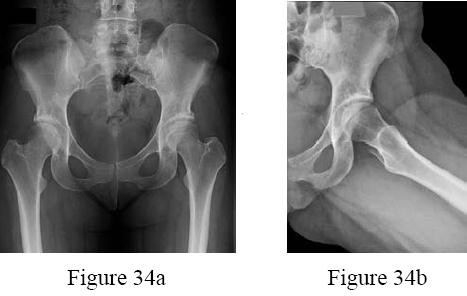

A 13-year-old overweight boy presents with a 3-week history of right groin and knee pain. He walks with a limp. On examination, when his right hip is flexed, it obligatorily externally rotates. Radiographs show a slip of the proximal femoral epiphysis. Which radiographic line is used to diagnose this condition?

Correct Answer: Klein's line

Explanation:

The clinical scenario describes Slipped Capital Femoral Epiphysis (SCFE). Klein's line is drawn along the superior edge of the femoral neck on an AP pelvic radiograph. In a normal hip, this line should intersect a portion of the lateral capital femoral epiphysis. In SCFE, the line passes superior to the epiphysis or intersects less of it compared to the contralateral normal side (Trethowan's sign).